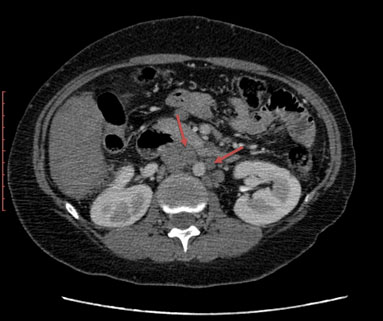

Abdominal CT showed multiple hepatic and splenic nodules enhanced after contrast injection, multiple peritoneal and retroperitoneal lymphadenopathies, and a lack of individualization of hepatic veins. The portal vein and its branches were permeable (Figure 1, Figure 2, Figure 3).

Figure 2: Abdominal CT showing inter-aortico-cava and lateroaortic adenopathies (red arrows).